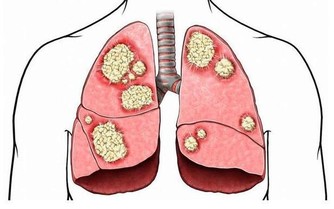

相較於燒烤,燙食對人體的危害更大。這種說法似乎有些聳人聽聞,但事實確實如此。機體的胃黏膜實際很脆弱,稍有不慎就會造成損傷。醫學界有個專業的術語叫做“化生”,這是一種常見的癌前病變,主要原因就是非本位細胞的替代生長。

我們就以“燙食”為例,熱乎乎的麵條下肚,穿過胃黏膜,很容易造成胃黏膜收縮甚至破損,為了修復損傷,機體就會在原處繼續生長新的細胞替代,但這個過程並不是十分嚴格,很容易發生錯誤,比如原本應該生長在腸道的細胞過來救急,長在了胃上,這就是化生,是完全錯誤的修補,時間長了,修補面積過多,很容易發展為胃癌。

我曾經受診過一名70多歲的老年患者,最近一段時間總是感覺腹脹,為求保險行胃鏡檢查,發現胃內有大面積的化生,病理結果顯示發現癌細胞,於外科緊急手術治療。和家屬討論病情,老伴就提到,老爺子吃了一輩子的燙食,最喜歡吃麵條、喝熱茶,永遠不嫌飯燙嘴。